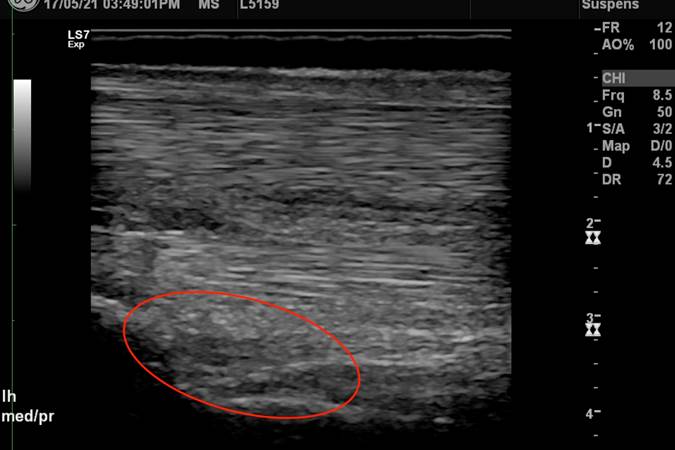

Suspensory desmitis